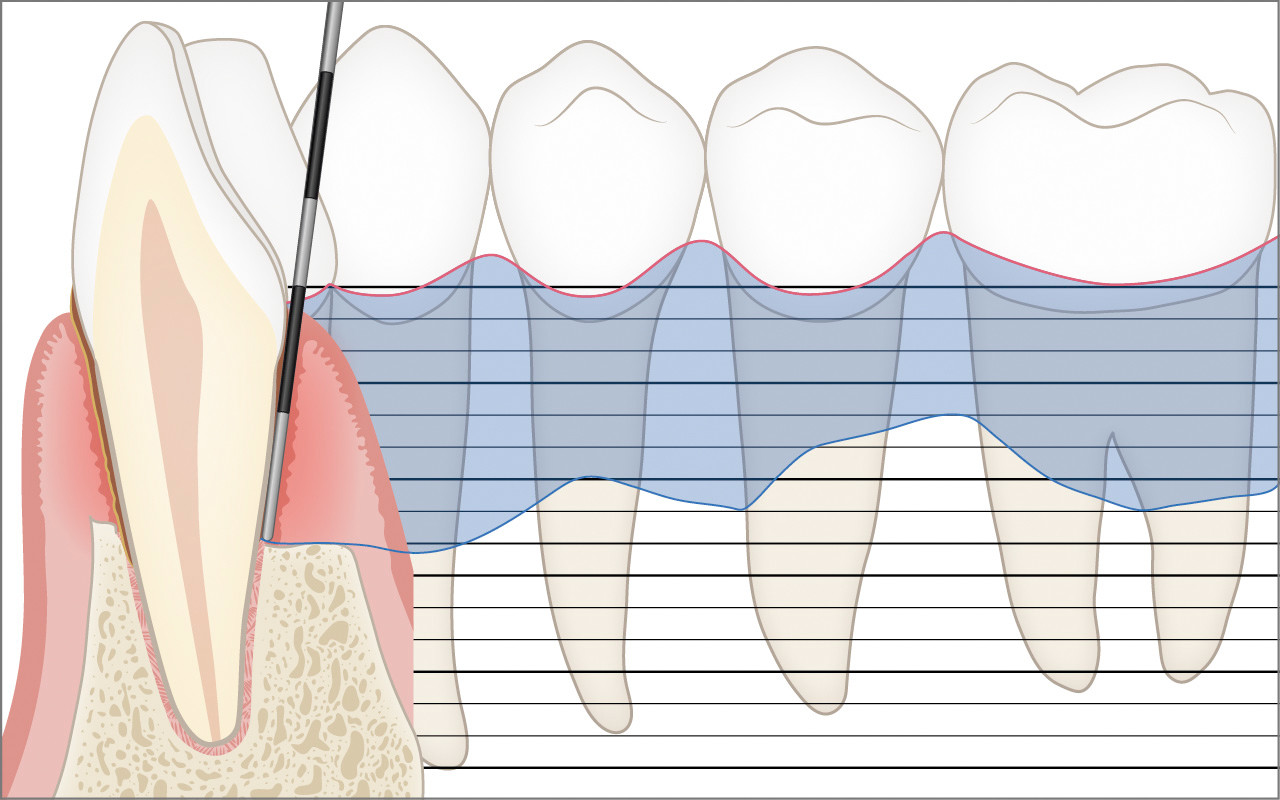

Die präzise klinische Sondierung mit der Parodontalsonde zur millimtergenauen Messung der Zahnfleischtaschen und der Höhe des Kieferknochens ist für die Diagnose der Parodontitis unerlässlich.

Bei der klinischen Untersuchung mit der Parodontalsonde wird die Eindringtiefe der Sonde in die Zahnfleischtasche an bis zu sechs Stellen pro Zahn millimetergenau gemessen. Dabei wird die Länge zwischen dem Zahnfleischrand und dem Taschenboden gemessen. Dies wird als Sondierungstiefe bezeichnet. Bei gesunden Stellen beträgt die Sondierungstiefe höchstens 3 mm. An Stellen, an denen die Parodontitis bereits zu einem Abbau der Zahnverankerung geführt hat, kann die Sondierungstiefe 4 mm oder mehr betragen.

Zusätzlich wird in einem so genannten Parodontalstatus die Höhe des Kieferknochens (Attachmentniveau) präzise aufgezeichnet. Ein Parodontalstatus ist für die Diagnose und die Behandlungsplanung unerlässlich. Der Parodontalstatus kann in jeder Zahnarztpraxis online aufgezeichnet und wiederverwendet werden: www.parodontalstatus.ch.

Die Messungen mit der Parodontalsonde können Stellen im Gebiss mit grösseren Sondierungstiefen aufspüren, die eine zusätzliche Beurteilung durch eine Röntgenaufnahme erfordern.